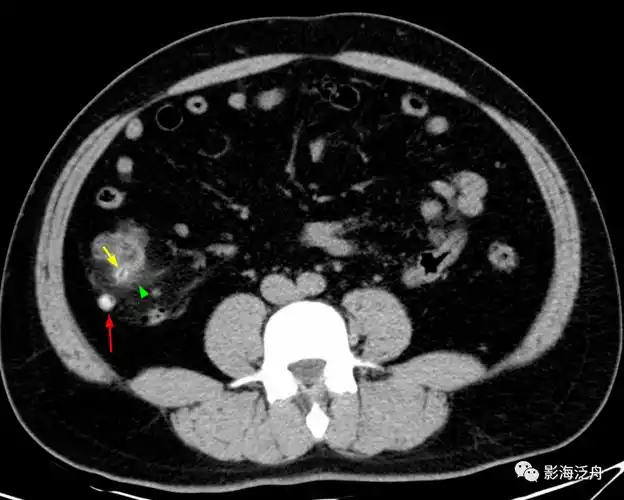

每日技能 | 病例分析之急性阑尾炎_诊断_复习_检查

小心误诊,这可不是急性阑尾炎!_盲肠_病例_诊断